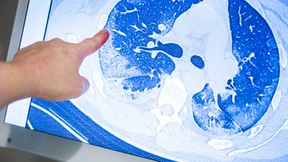

An der Wiesbadener DKD Helios Klinik ist ein Behandlungskonzept für Patienten mit Corona-Spätfolgen entwickelt worden. Das interdisziplinäre Angebot der Klinik kann bei verschiedenen Beschwerden helfen.